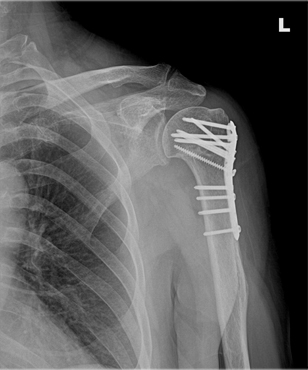

x-ray 사진

상완골 경부 골절, 수술 전

상완골 경부 골절, 수술 후